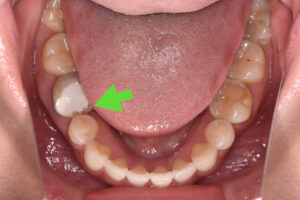

歯は一度削ったり抜いたりすると元には戻りません。できれば自分の歯を残したいと思う方が多いのではないのでしょうか。マイクロスコープを用いると、虫歯に汚染された部分を正確に捉えることができるため「なるべく歯を削らない」「なるべく神経を取らない」「組織を温存する」治療が可能となります。さらに虫歯の再発を防ぐ事にもつながるのです。

歯科治療は「虫歯に汚染された部位を削る」「歯の根の中の汚染された神経を除去する」など、細かい部位の細かな手技の連続です。肉眼(裸眼)では患部の細部まで捉えきれないため、マイクロスコープは歯科治療においては欠かせない器具だと考えております。マイクロスコープを活用すれば肉眼の約20倍の拡大率で治療ができるため、より精密な治療に繋げることができます。ただマイクロスコープは、すべての歯科医院に完備されてるわけではありません。歯科医院全体における普及率は約10%ほどです。マイクロスコープがない歯科医院では、レントゲン写真を参考に経験や勘に頼って歯科治療を行っているケースが少なくない状況です。その結果、虫歯の取り残しや歯の削りすぎ、汚染物質の取り残しなどが起こることがあるのです。マイクロスコープを使えば、虫歯に汚染された部分を正確に捉えて削ることに繋がります。

必要以上に患者様の健康な歯質を削ったり、虫歯を取り残して再治療をしたりするリスクが減るのです。ご自分の歯を活かしたキレイな歯をご提供することが可能となるのです。当院の院長は、PIFというマイクロスコープのグループに所属し、マイクロスコープの使用方法などのインストラクターとしても仕事をしております。

歯科用マイクロスコープとは、肉眼の約20倍まで拡大できる歯科用顕微鏡です。目に見えない部分にいたるまで、精密で正確な治療に繋げることができます。

当院ではほぼ全ての一般診療にマイクロスコープを使用した精密な治療を提供しております。